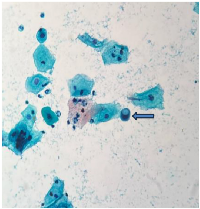

The smear was prepared using the conventional Papanicolaou (Pap) staining method and examined microscopically. Microscopy revealed a moderately cellular smear. Numerous squamous epithelial cells exhibited: Nuclear enlargement with preserved N:C ratio, Cytoplasmic vacuolation and granularity, Mild hyperchromasia with smudged chromatin, Binucleation and multinucleation, Degenerative nuclear changes such as nuclear pallor, irregular membranes, and chromatin wrinkling, Occasional bizarre-shaped cells and Inflammatory background with atrophy. No malignant cells were seen. (Figures 13) Considering the patient’s history and the morphological features, final cytological diagnosis was given as Post-radiation changes, no evidence of malignancy. At 12-month follow-up, the patient remained clinically stable and asymptomatic. Continued cytological surveillance was advised.

Smear shows cytoplasmic projection (Pap stain, 400×).

Figure 2: Smear shows cytoplasmic projection (Pap stain, 400×).

Smear shows a cell with cytoplasmic vacuolation (Pap stain, 400×).

Figure 3: Smear shows a cell with cytoplasmic vacuolation (Pap stain, 400×).